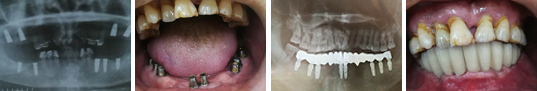

人工种植牙通常可以长久使用。经调查发现人工种植牙的脱落率低于人类自然牙的脱落率。有40年以上还在完好使用的人工种植牙的病例。

可以解决传统镶牙方法无法解决的疑难问题。

开展人工种植牙应有配套的种植牙设备和材料的医院或诊所,由经过人工种植牙专业培训的医师和义齿制作技师进行。 目前我市开展人工种植牙工作清花园口腔门诊是最早的,并获市新技术应用三等奖。

清花园口腔门诊具有全套高品质德国人工种植牙设备和材料:采用德国设计生产的国际上最 先进的人工种植牙系统。拥有高素质的人工种植牙团队。种植牙医师和义齿加工技师都多次 接受德国著名专家的高级培训。已完成的人工种植牙病例,可以达到国际先进水平。获市新技术应用三等奖。